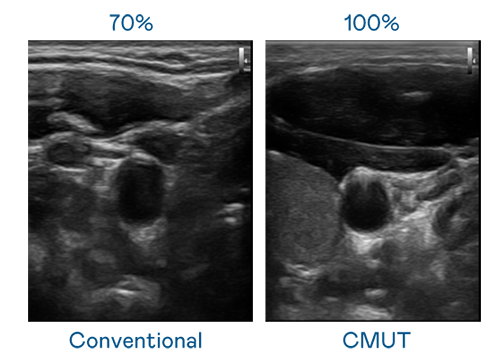

CMUT 技术是一种用电容式微机电元件来产生超音波讯号的技术。与传统 PZT 压电式技术相比,CMUT 频宽增加 30%,更宽频的超音波讯号让影像解析度大幅提升,是实现高影像品质医疗超音波扫描、促进精准医疗发展的关键技术。

大频宽带来超清晰影像

超音波影像的解析度高低,首先取决于探头能发出的讯号频宽。ag博天堂 CMUT 可提供高清晰的超音波讯号,提供高频宽、高灵敏度、影像纹理细节更高的超音波影像,协助医护人员缩短影像判读时间及利用精准的医疗影像进行诊断。